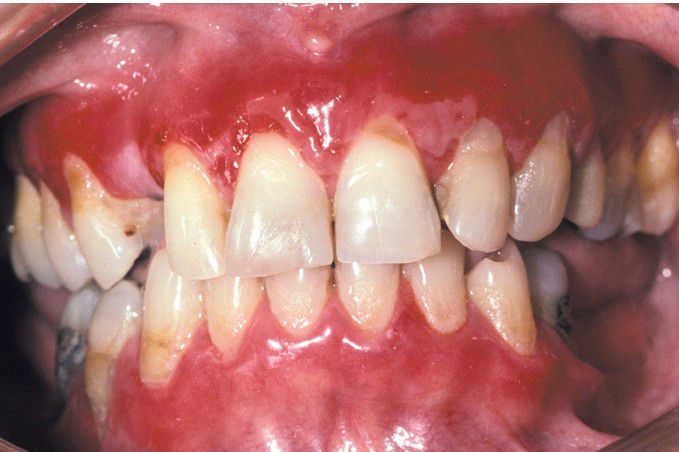

Mucous Membrane Pemphigoid

Often the gingival tissues are the only affected site, resulting in a clinical pattern known as desquamative gingivitis. Such a pattern may also be seen with lichen planus and pemphigus vulgaris.